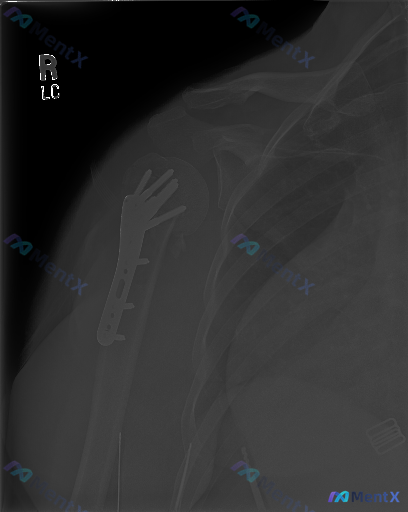

整理到一张左前臂(含肘关节)的X光复查片,先抛出来给大家看看。 影像里明确能看到的: 1. 尺骨和桡骨近段都有金属接骨板+多枚螺钉固定 2. 内固定物位置看起来还稳,没有明显断钉、松动或钢板断裂 3. 肘关节各个关节对位正常,间隙也清 4. 周围软组织没有明显肿胀 但有个细节有点意思: 接骨板覆盖的...